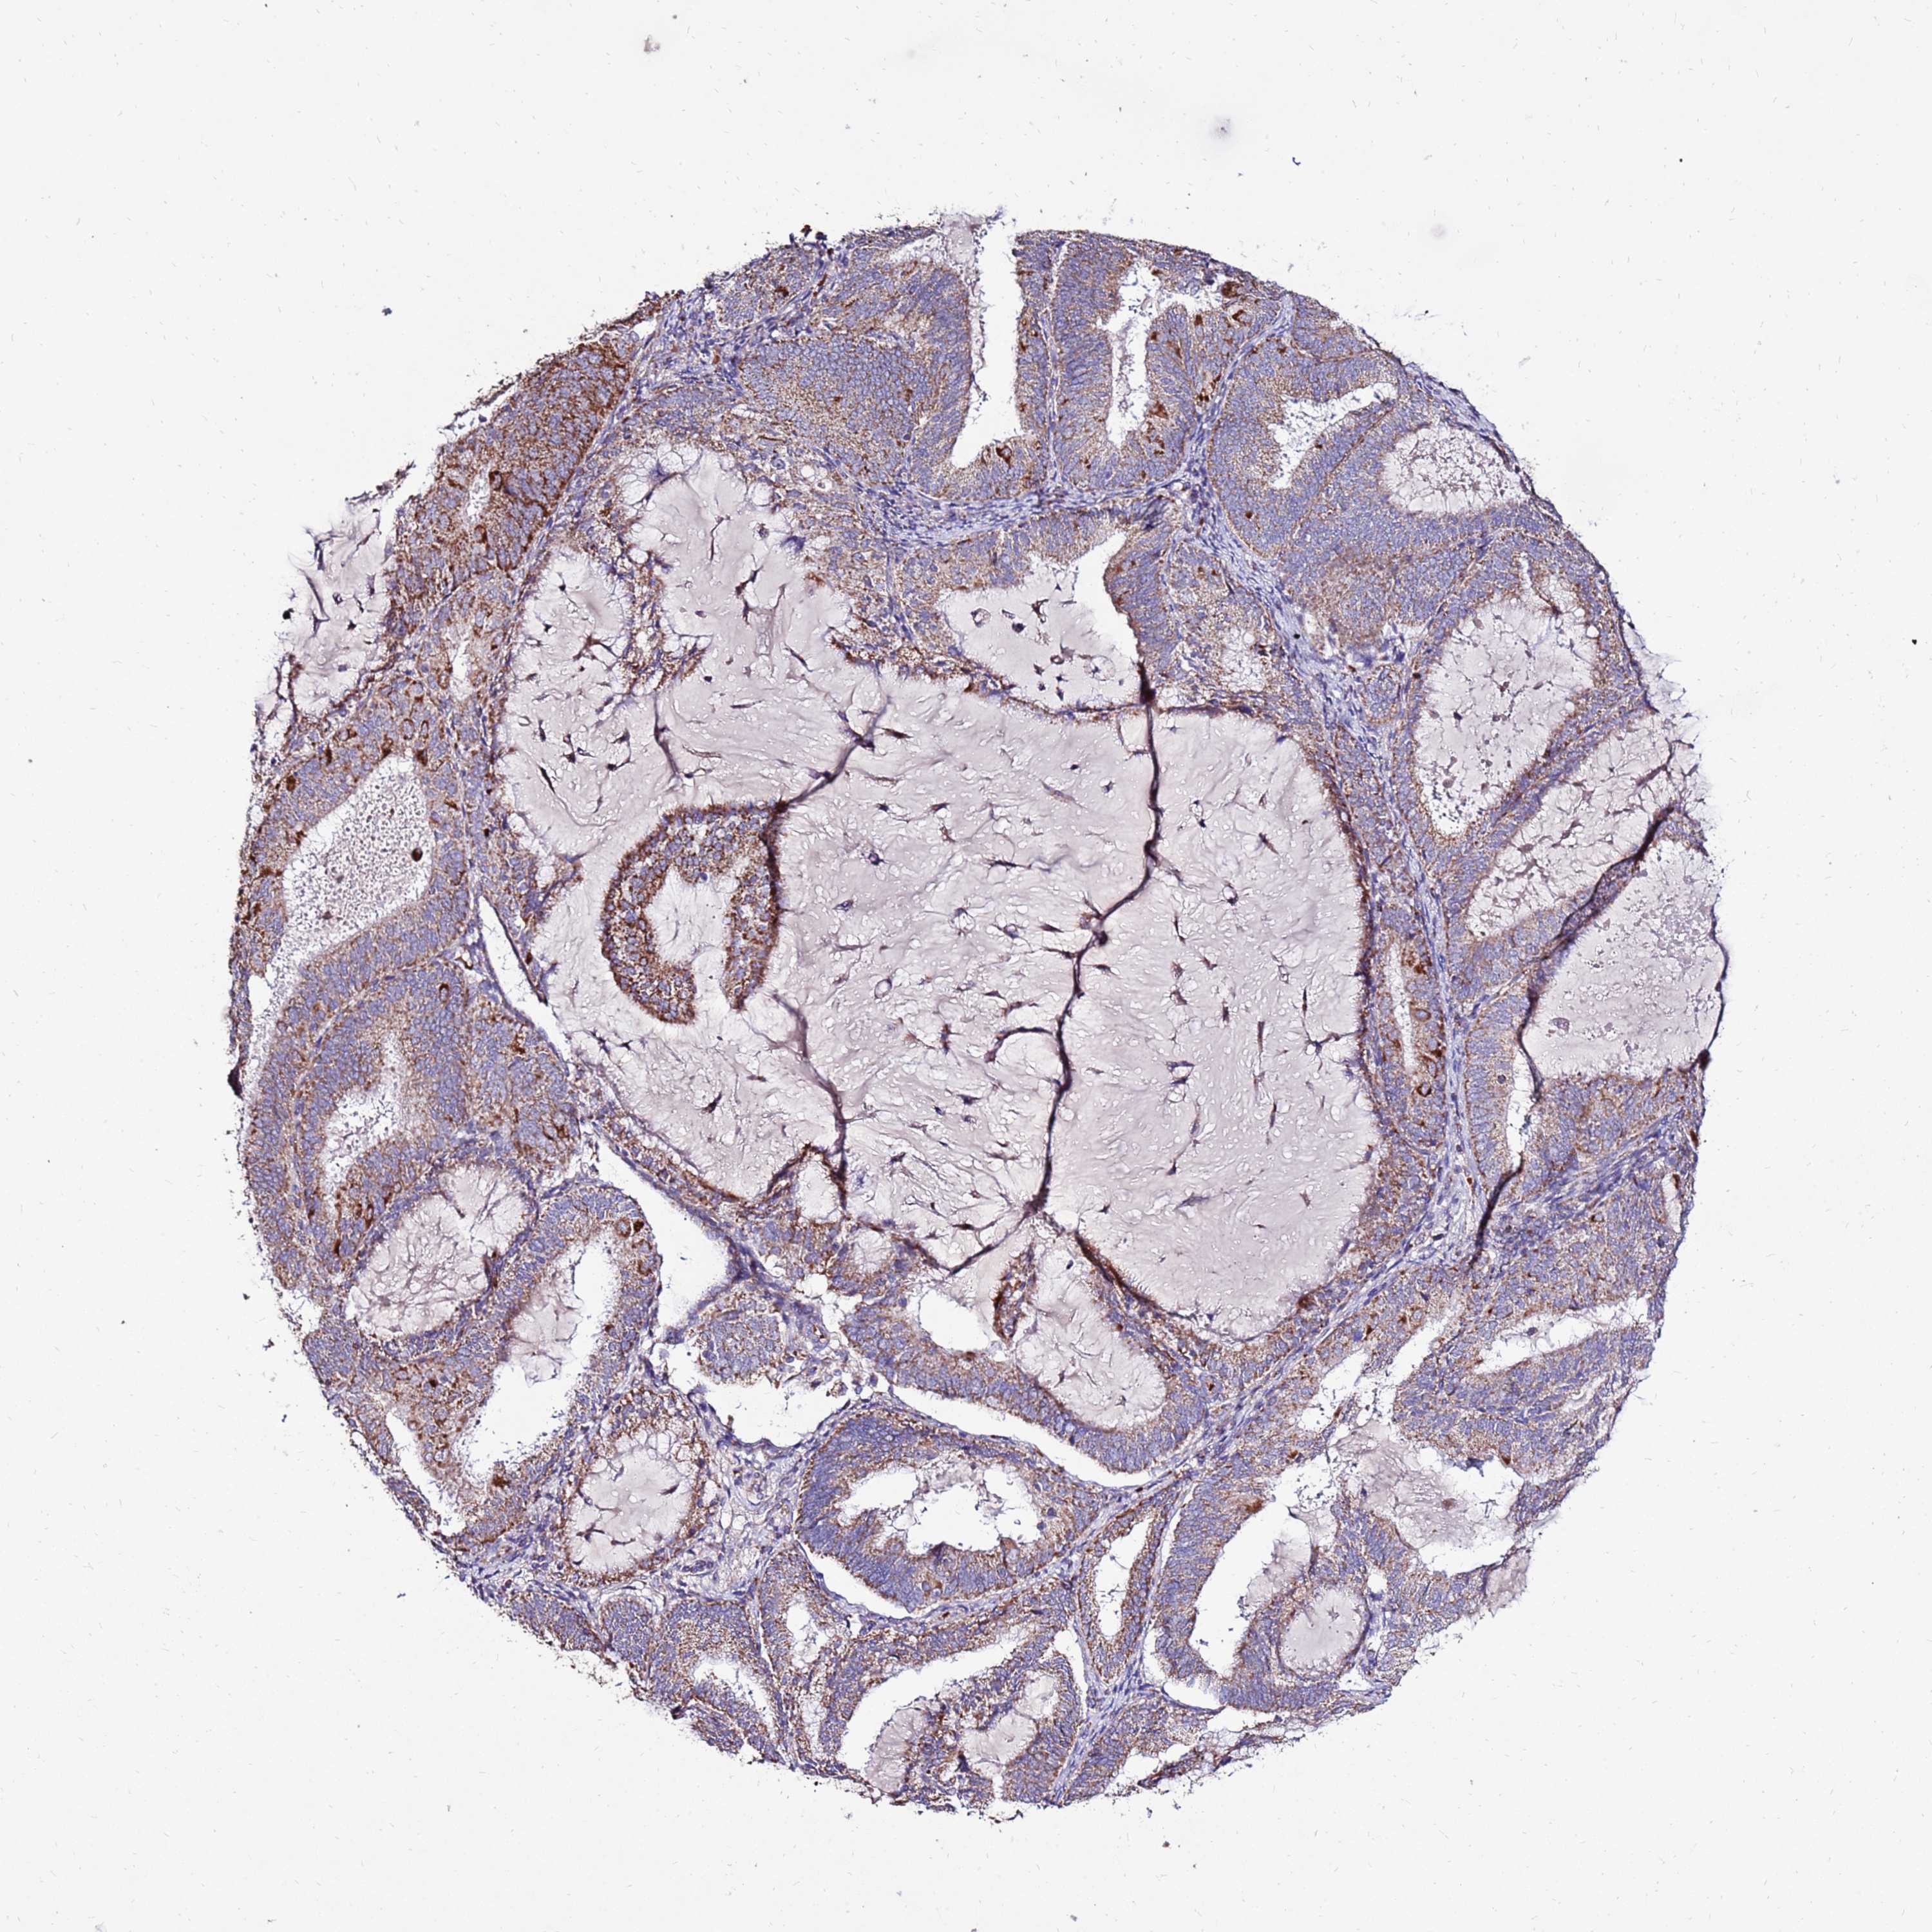

ENDOMETRIAL CANCER - Protein expressioni

A mouse-over function shows sample information and annotation data. Click on an image to view it in a full screen mode. Samples can be filtered based on level of antibody staining by selecting one or several of the following categories: high, medium, low and not detected. The assay and annotation is described here.

Note that samples used for immunohistochemistry by the Human Protein Atlas do not correspond to samples in the TCGA dataset.

Antibody stainingi

Antibody staining in the annotated cell types in the current human tissue is reported as not detected, low, medium, or high, based on conventional immunohistochemistry profiling in selected tissues. This score is based on the combination of the staining intensity and fraction of stained cells.

Each image is clickable and will lead to virtual microscopy that enables deeper exploration of all samples and also displays staining intensity scores, fraction scores and subcellular localization as well as patient and tissue information for each sample.

Antibody HPA046602

Staining

High

Medium

Low

Not detected

Intensity

Strong

Moderate

Weak

Negative

Quantity

>75%

75%-25%

<25%

None

Location

Nuclear

Cytoplasmic/membranous

Cytoplasmic/membranous,nuclear

Adenocarcinoma, NOS